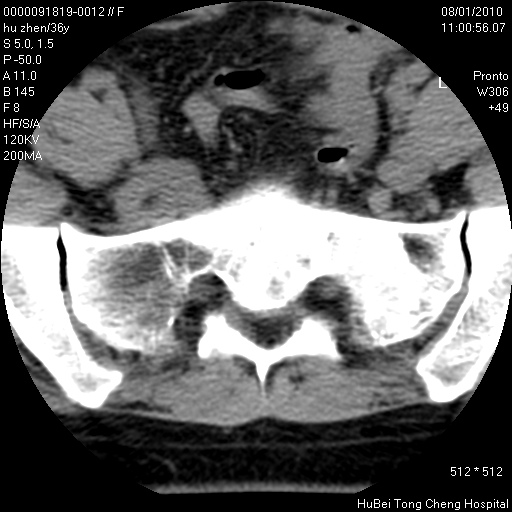

患者 女,36岁。右侧腰腿痛半月余。腰骶椎mr平扫偶然发现骶椎异常信号。

临床诊断:1)腰椎间盘突出症。2)骶椎肿瘤性病变?

骶椎ct平扫(层厚、层距均为5mm),图像如下: